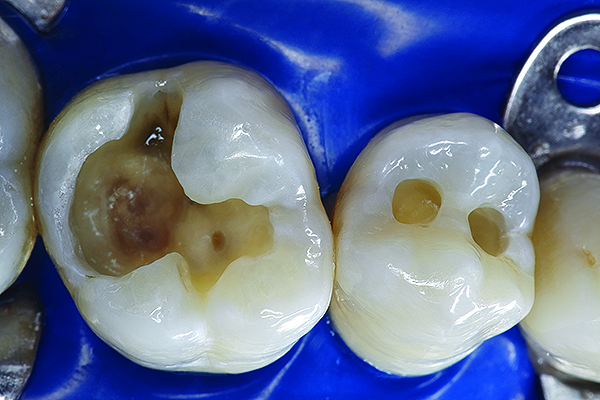

Unfortunately, many clinicians continue to perform outdated procedures with modern restorative materials, and then wonder why they continue to have microleakage, recurrent decay, and sensitivity. Advances in material science and adhesive technology require clinicians to modify their restorative techniques when placing adhesive restorations. This is particularly true when one is considering diagnosis, biomaterial selection, preparation design, restorative placement techniques, pulp protection, finishing, and maintenance.17 The adhesive design concept requires the selection of adhesive, bioactive restorative materials; simplified modifications of preparation designs; and precise placement procedures and techniques. This design concept has been instrumental in the paradigm shift from the principles of extension for prevention to the ultraconservative principle of prevention to eliminate extension. The proper interrelation of these restorative parameters—biomaterial selection, adhesion, and technique—can result in an optimal restorative–tooth interface with improved clinical performance (Figure 1), whereas an improper interrelation can lead to gap formation, microleakage, staining, sensitivity, caries, and partial or complete debonding of the restoration that can result in long-term clinical failure (Figure 2).18

Figure 7. The occlusal outline was extended only to include carious enamel, provide access to the carious dentin, and remove any residual amalgam staining.